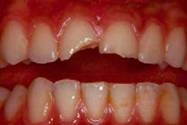

Case 2

missing

Before

After